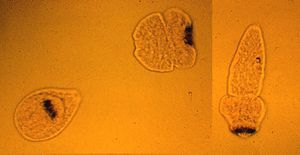

مرض المكورات الشوكية Echinococcosis ، هي أكياس تحتوي على سائل مائي، وتوجد في أنسجة الإنسان والأغنام وبعض الحيوانات الأخرى. وتعد يرقات الدودة الشريطية من مسببات هذا المرض وأساس تكوينه. ويشكّل هذا المرض خطورة كبيرة على الإنسان. ويمكن للكلاب أن تحمل عدوى هذا المرض. فمثلاً إذا عبث كلب بفضلات الأغنام التي تحتوي على الأكياس، يمكن ليرقات الدودة الشريطية أن تلتصق بشعر هذا الكلب. ثم ينتقل المرض إلى المتعاملين مع الكلاب. كما يمكن أن ينتقل المرض للإنسان عن طريق تناول الخضراوات غير المطبوخة أو شُرب المياه ملوثة. ويعد هذا المرض مشكلة أساسية من مشكلات الصحة في البلاد التي تنتشر فيها تربية الأغنام.